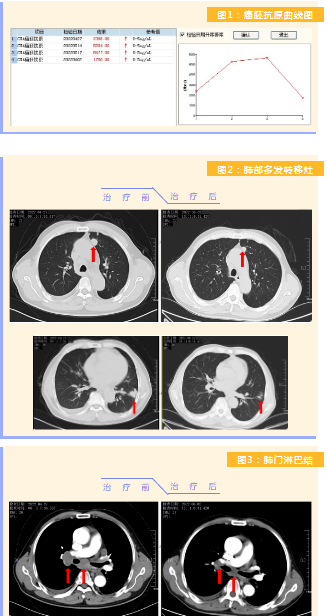

患者完成1周期治療后,上腹部疼痛癥狀基本消失,梗阻性黃疸癥狀緩解,腫瘤指標(biāo)下降(圖1),肺部多發(fā)轉(zhuǎn)移灶消失和縮?。▓D2),雙肺門淋巴結(jié)縮小(圖3),肝臟多發(fā)轉(zhuǎn)移灶縮?。▓D4)。